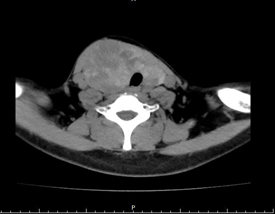

术前检查发现,余女士甲状腺右叶结节达到 10*7*5 厘米大小,气管明显受压移位。因患有慢性肾功能衰竭、肥厚型心肌病、高血压病 3 级,2 型糖尿病等多种内科疾病,长期血液透析治疗,余女士及家属对手术治疗有一定的顾虑。